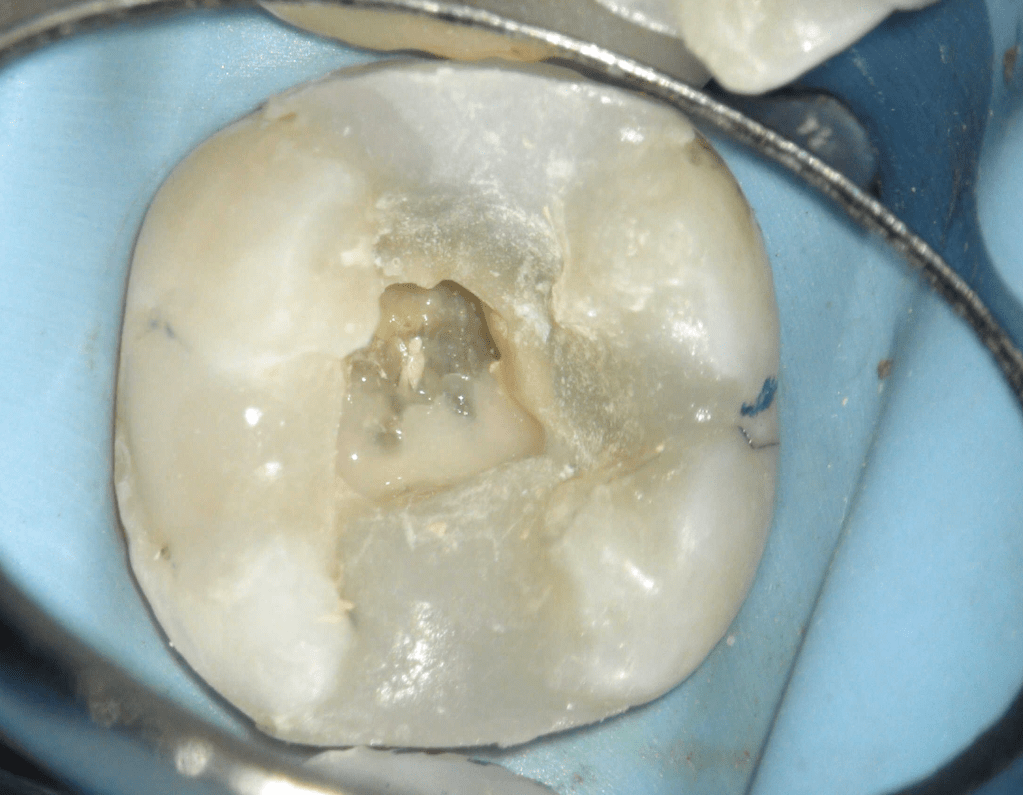

Reco pared vesticular